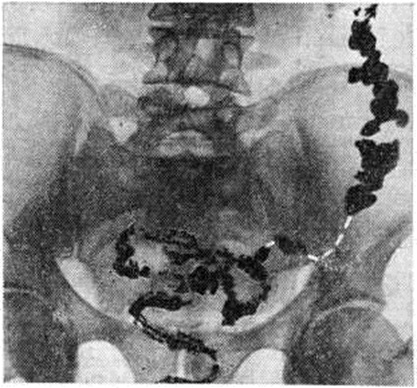

ДиагнозДиагноз устанавливают обычно на основании анамнеза и жалоб больного. Важно выяснение этиологии и типа Запоры, особенно своевременное распознавание опухолевых процессов, вызывающих механический Запоры; при этом наряду с клинический, данными (пожилой возраст, недавнее начало Запоры у лиц с нормальным стулом, примесь крови в кале и другие) большое, диагностическое значение приобретает рентгенологическое исследование, колоноскопия (смотри полный свод знаний), ректор оманоскопия (смотри полный свод знаний). При ректороманоскопии в случае гипермоторики слизистая оболочка прямой и сигмовидной кишок влажная, видна перистальтика, спазмы, окраска слизистой оболочки меняется быстро, при гипомоторике — слизистая оболочка сухая, тусклая, дистальный отдел толстой кишки в спавшемся состоянии, продвижение тубуса затруднено. Известные трудности возникают при дифференциации воспалительных Запоры при колитах и Запоры преимущественно функциональной природы. Распознаванию природы и дифференциации Запоры способствует копрологические исследование (смотри полный свод знаний Кал), биопсия слизистой оболочки прямой или сигмовидной кишки. Большое значение имеет определение типа моторных нарушений толстой кишки. Некоторые данные могут быть получены при пальпации: при преимущественно гипермоторных нарушениях дистальных отделов толстой кишки сигмовидная кишка спастически сокращена, при гипомоторных нарушениях она может быть растянута, не перистальтирует. Важную информацию даёт запись моторики кишечника баллонотензографическим методом. Рентгенологическое исследование имеет целью выявить нарушения моторной функции и тонуса толстой кишки, первичный или вторичный Запоры Его проводят спустя определённые промежутки времени после приёма внутрь бариевой взвеси — через 4— 6—9—12—24—48 часов и позже. Основное внимание обращают на характер заполнения и опорожнения кишки, пассажа по ней бария, вид гаустр, наличие спастических сокращений, а также скоплений газа и жидкости. К ирригоскопии (смотри полный свод знаний) прибегают в случаях, когда необходимо исключить аномалию развития кишки или её органическое поражение, при которых Запоры (вторичный) может быть симптомом заболевания. При первичных Запоры обычно обнаруживают снижение моторной функции, повышение, или понижение тонуса кишки. Эти изменения могут распространяться на всю кишку или на отдельные её сегменты (рисунок 1). Рельеф слизистой оболочки имеет нормальный или несколько «раздражённый» характер (ирритационный рельеф): складки приподняты, расположены более продольно или поперечно, но лишены, признаков воспаления. Смещаемость кишки не нарушена. При гиперкинетических Запоры замедление пассажа бария сочетается с регионарным спазмом и глубокой, нередко сегментирующей гаустрацией в виде многочисленных перетяжек (рисунок 2). Спазмированный отдел кишки иногда имеет вид тонкого шнура (рисунок 3). Реже, при атонических Запоры, обнаруживают пониженный тонус всей толстой кишки или отдельных её сегментов, сопровождающийся расширением просвета, поверхностной сглаженной гаустрацией.